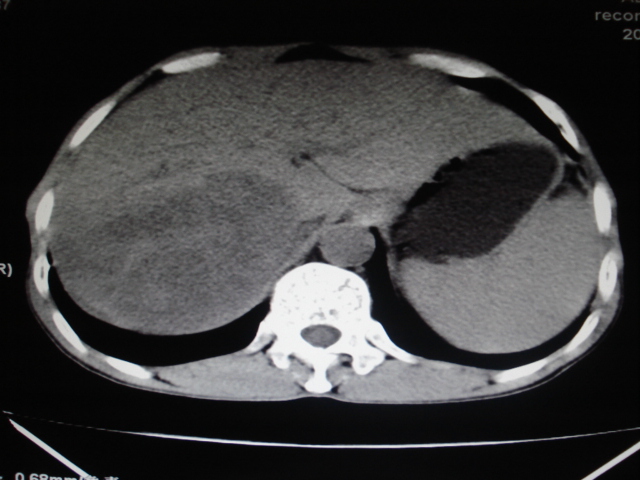

标题: CT24041:肝脏占位,请会诊!

男性,62岁。肝右叶占位,平扫及增强如下,延迟期为15分钟扫描。

局限性脂肪浸润。

支持局限性脂肪肝的诊断

支持局限性脂肪肝,右肾囊肿.